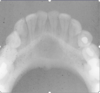

What is this radiographical finding?

Metastatic Carcinoma to Jaw Bones

C. Periapical image of a metastatic lesion of breast carcinoma; note the irregular widening of the periodontal membrane spaces and patchy sclerotic bone reaction, especially around the roots of the molars